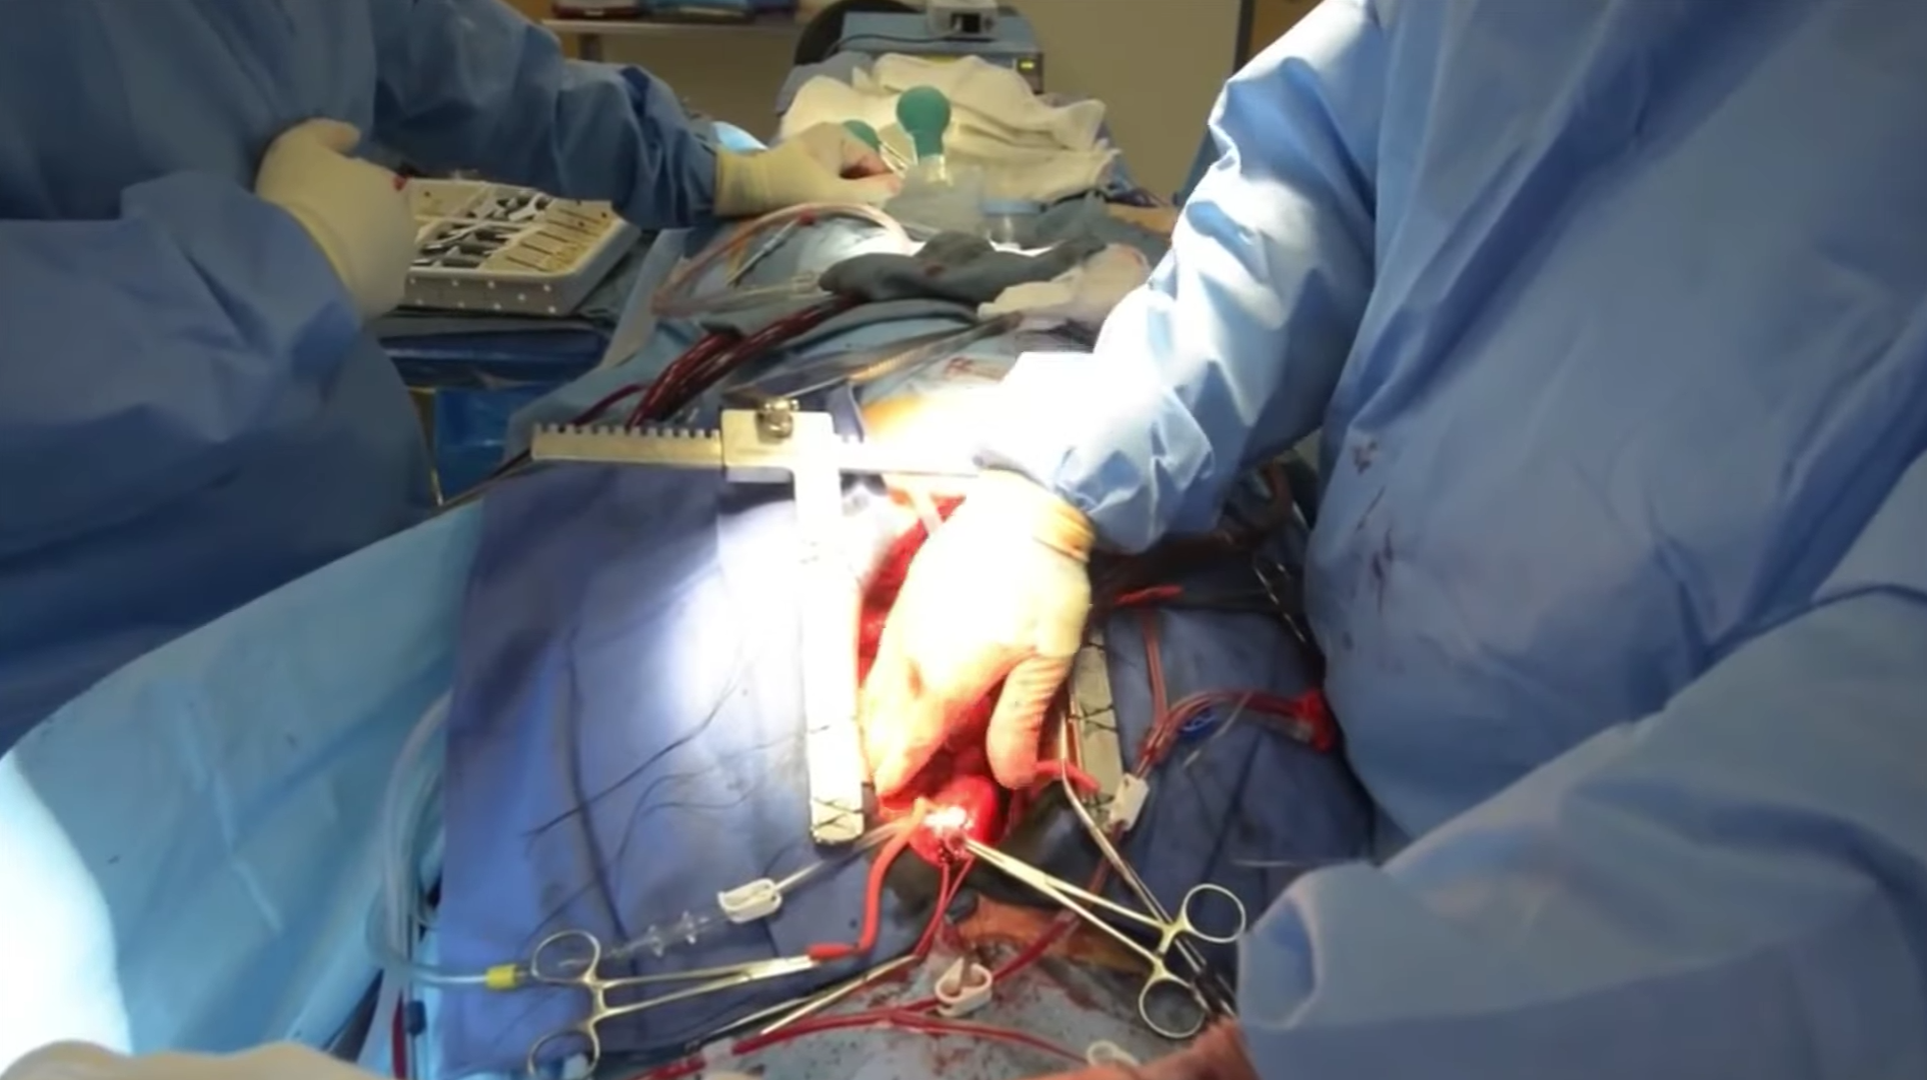

Cilt Grefti Uygulaması

Cilt Grefti Uygulaması

Cilt Grefti Uygulaması